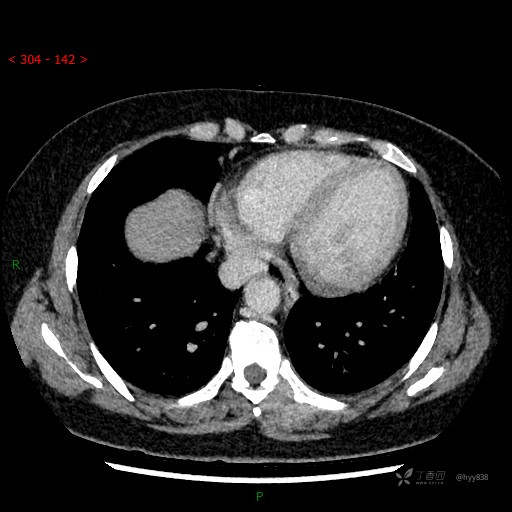

增强